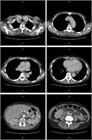

1. 巨細胞性動脈炎(Giant cell arthritis、GCAは、大多数の例では頭部症状(頭痛・頭皮の圧痛・下顎跛行・複視・視力消失)や発熱、リウマチ性多発筋痛症様の症状などで発症するが、10-15%は発熱のみ、また4%は上気道症状を初めとする非典型的な症状で発症することがある